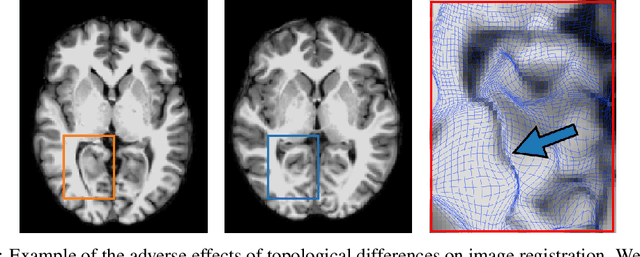

Abstract:Geometric alignment appears in a variety of applications, ranging from domain adaptation, optimal transport, and normalizing flows in machine learning; optical flow and learned augmentation in computer vision and deformable registration within biomedical imaging. A recurring challenge is the alignment of domains whose topology is not the same; a problem that is routinely ignored, potentially introducing bias in downstream analysis. As a first step towards solving such alignment problems, we propose an unsupervised topological difference detection algorithm. The model is based on a conditional variational auto-encoder and detects topological anomalies with regards to a reference alongside the registration step. We consider both a) topological changes in the image under spatial variation and b) unexpected transformations. Our approach is validated on a proxy task of unsupervised anomaly detection in images.